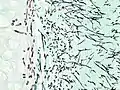

On microscopy, Aspergillus species are reliably demonstrated by silver stains, e.g., Gridley stain or Gomori methenamine-silver.[27] These give the fungal walls a gray-black colour. The hyphae of Aspergillus species range in diameter from 2.5 to 4.5 μm. They have septate hyphae,[28] but these are not always apparent, and in such cases they may be mistaken for Zygomycota.[27] Aspergillus hyphae tend to have dichotomous branching that is progressive and primarily at acute angles of around 45°.[27]